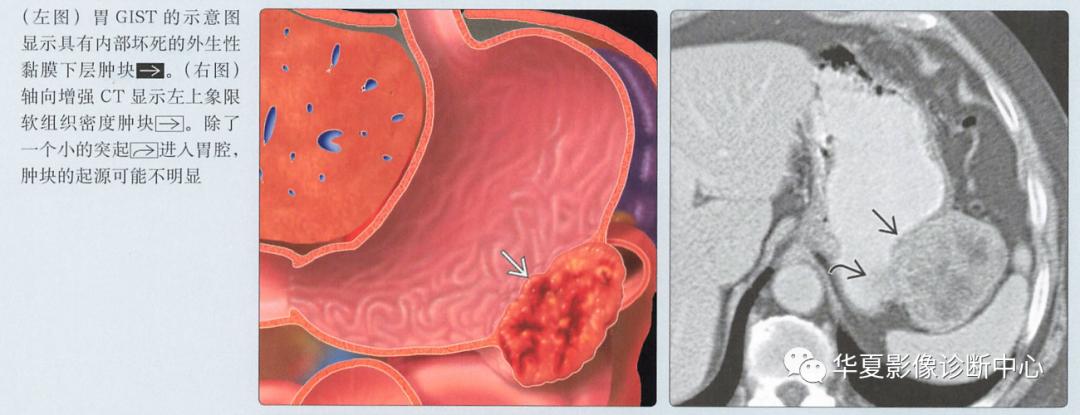

边界光整,黏膜下层肿块向消化道外生性生长

通常是外生的,可能有囊性成分

圆形,外生性黏膜下胃肿块

溃疡在较大的肿块中很常见

肿瘤的中心坏死可能充满钡餐

增强CT

动脉期图像呈低或高血供,边界清楚的黏膜下肿块;溃疡和坏死是常见的

具有大的腔内成分的肿瘤可能类似原发性胃癌